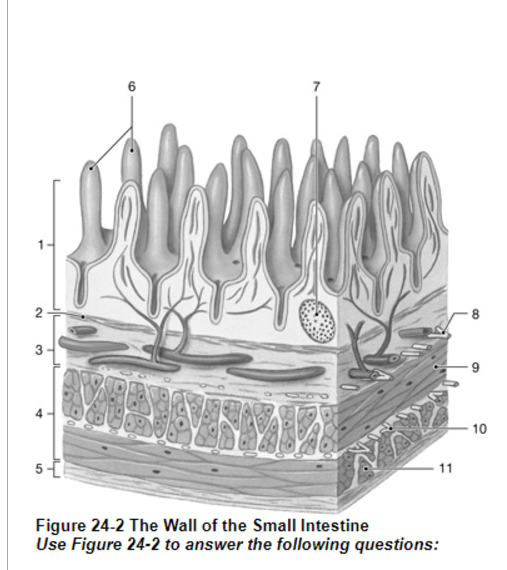

What is the layer labeled “4”?

Muscularis externa

What is the layer labeled “2”?

Muscularis mucosae

What is the layer labeled “3”?

submucosa

Which structure controls the contraction of the muscularis externa?

10